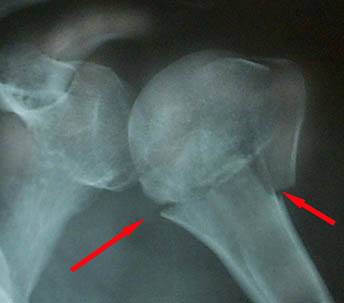

Перелом плечевой кости (рентгенограмма)